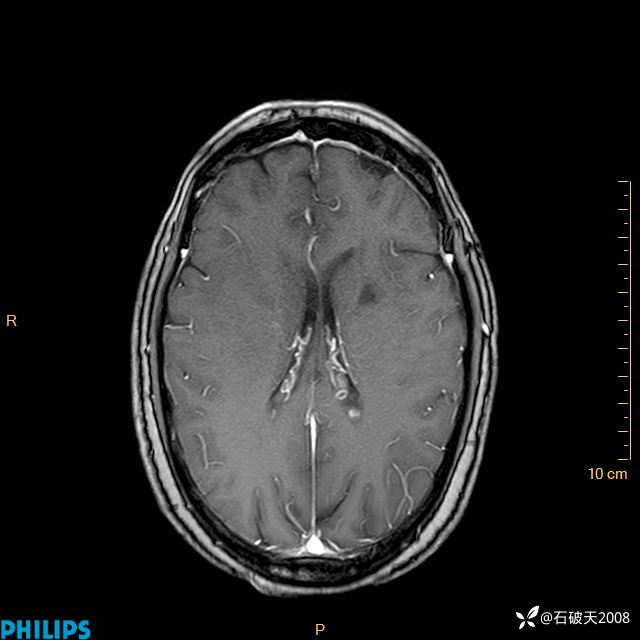

2020.11.14MR

增强轴位